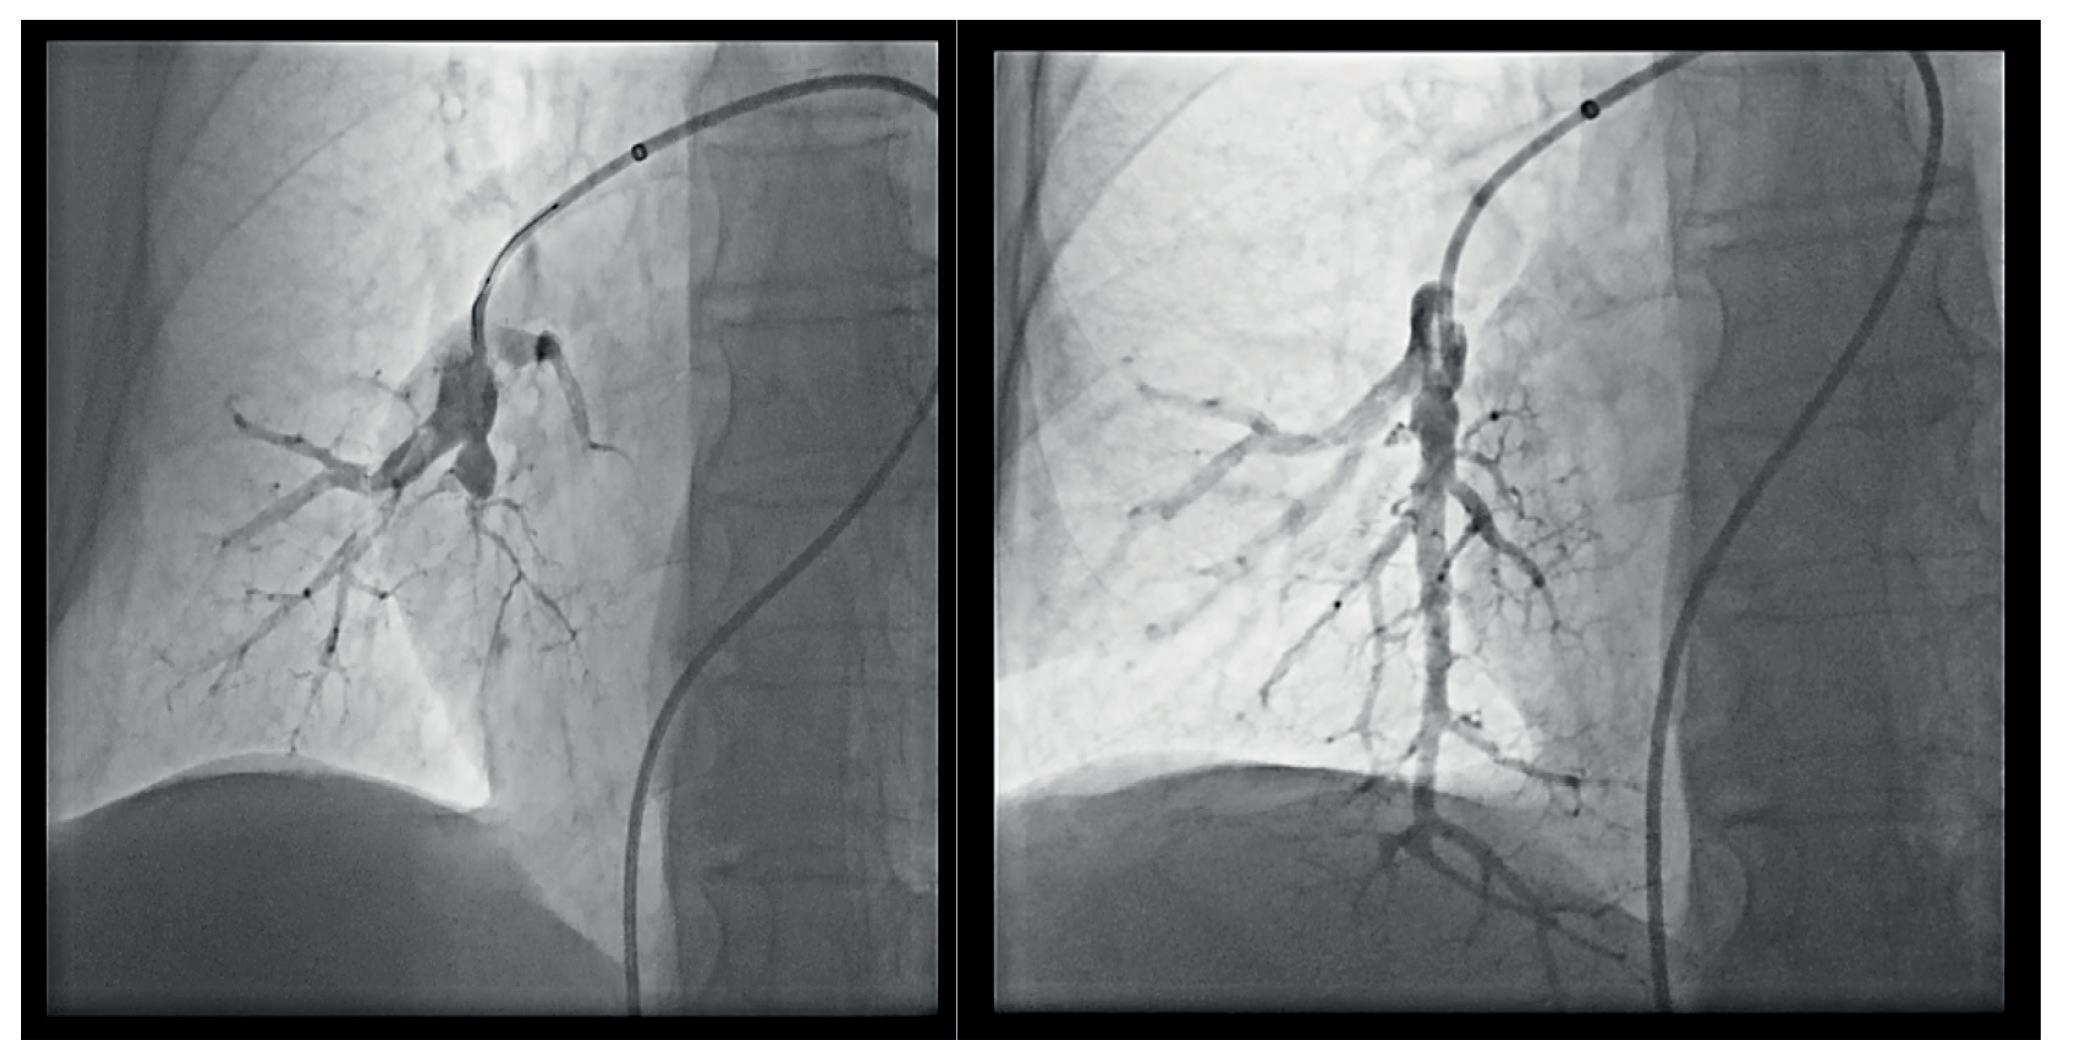

Άρθρο-Καρδιολογία

Παναγιώτης Καριοφύλλης: Θεραπεία της

ανεγχείρητης Χρόνιας Θρομβοεμβολικής

Πνευμονικής Υπέρτασης 60